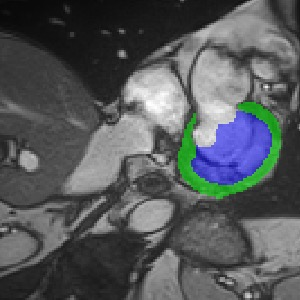

Transformers, the default model of choices in natural language processing, have drawn scant attention from the medical imaging community. Given the ability to exploit long-term dependencies, transformers are promising to help atypical convolutional neural networks (convnets) to overcome its inherent shortcomings of spatial inductive bias. However, most of recently proposed transformer-based segmentation approaches simply treated transformers as assisted modules to help encode global context into convolutional representations without investigating how to optimally combine self-attention (i.e., the core of transformers) with convolution. To address this issue, in this paper, we introduce nnFormer (i.e., Not-aNother transFormer), a powerful segmentation model with an interleaved architecture based on empirical combination of self-attention and convolution. In practice, nnFormer learns volumetric representations from 3D local volumes. Compared to the naive voxel-level self-attention implementation, such volume-based operations help to reduce the computational complexity by approximate 98% and 99.5% on Synapse and ACDC datasets, respectively. In comparison to prior-art network configurations, nnFormer achieves tremendous improvements over previous transformer-based methods on two commonly used datasets Synapse and ACDC. For instance, nnFormer outperforms Swin-UNet by over 7 percents on Synapse. Even when compared to nnUNet, currently the best performing fully-convolutional medical segmentation network, nnFormer still provides slightly better performance on Synapse and ACDC.